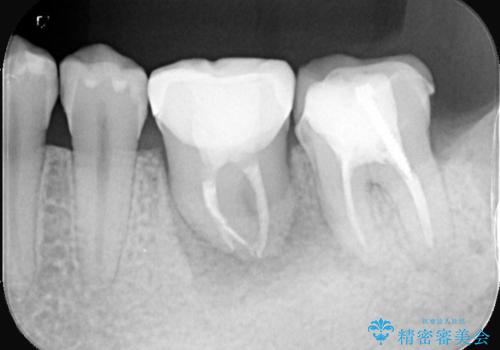

保存が難しい左下6番目の歯を抜歯し、左下8番目の歯(親知らず)を抜歯窩に移植しました。歯牙移植後の動揺防止のため暫間固定を行っています。

骨との定着を確認し、今後矯正治療を行う予定のためレジン冠をセットしています。